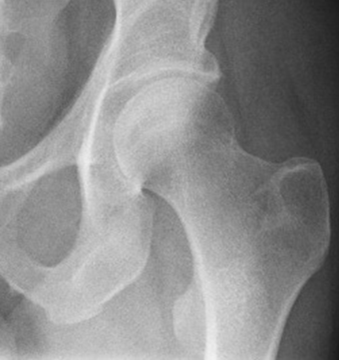

НЕОПЕРОВАНИЙ ПЕРЕЛОМ ЦІЄЇ КІСТКИ І В ЦЬОМУ МІСЦІ ПРИЗВЕДЕ ДО СМЕРТІ В СЕРЕДНЬОМУ ЧЕРЕЗ КІЛЬКА РОКІВ. А ЦІ РОКИ ПЕРЕТВОРЯТЬСЯ НА СИДЯЧІ АБО ЛЕЖАЧІ МУКИ. ЯКОЇ КІСТКИ І ЯКОЇ ЇЇ ЧАСТИНИ?

варіанти відповідей

HUMERUS, ХІРУРГІЧНА ШИЙКА

ВЕРХНЬОГО ДІАФІЗА

FEMUR, ШИЙКА

ULNA, ШИЙКА

ПРОКСИМАЛЬНОГО ЕПІФІЗА

ДИСТАЛЬНОГО ЕПІФІЗА

HUMERUS, ШИЙКА

RADIUS, ШИЙКА